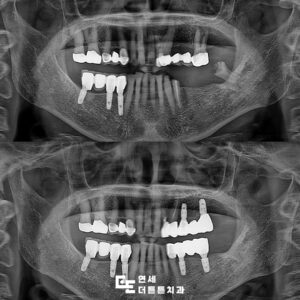

수락산역치과, 예후가 좋지 않은 치아들 발치 후 전체 임플란트

수락산역치과, 예후가 좋지 않은 치아들 발치 후 전체 임플란트   치아가 여러 개 없으면 단순히 음식을 씹는 즐거움만 줄어드는 것이 아닙니다.   저작 능력이 떨어지면 소화 부담이 커지고 영양 섭취의 균형도 무너질 수 있으며, 상태가 악화될 경우 얼굴 균형 변화나 인지 기능 저하와 같은 전신 문제로 이어질 가능성도 있습니다.   더보기…